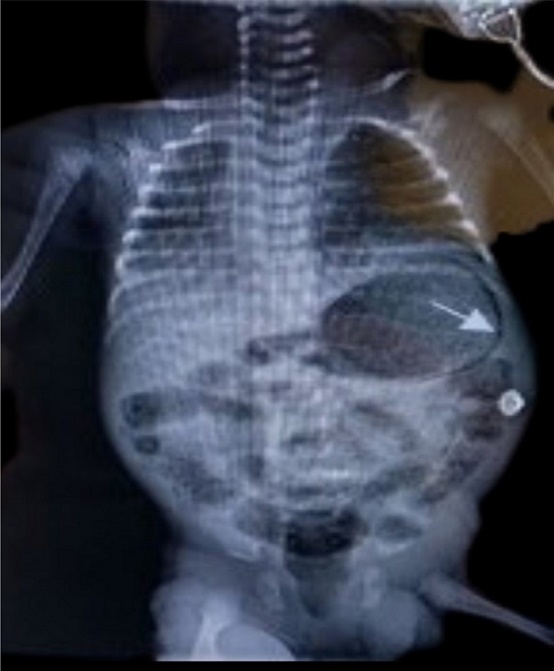

A late preterm (gestational age 35+2/40) male neonate was born to a 25-year-old multiparous woman with minimal antenatal care (5 visits). Her booking parameters were unremarkable and her antenatal period reportedly uneventful. She presented with preterm, prolonged, pre-labour rupture of membranes (PPPROM) and was therefore induced with Cytotec® (Misoprostol); liquor was said to be clear. There were no signs of chorioamnionitis and no antibiotics or steroids were given during delivery. He was delivered via spontaneous vaginal delivery (SVD), and was suctioned; nil other active resuscitation was required. APGARs were 9 and 9 at 1 and 5 minutes respectively. Essential newborn care was offered. Initial examination was unremarkable with temperature of 36.8◦C. He was of low birth weight at 2.46 kg. He was allowed to room in with his mother on the postnatal ward; however by 6 hours of life he was notably distressed characterized by grunting and accessory muscle use, despite a normal respiratory rate of 56. Pre and post ductal saturations were acceptable (97% respectively).Given the presence of danger signs and his history of prematurity on a background of PPPROM, he was admitted to the Neonatal Intensive Care Unit (NICU), nursed in an isolette, attached to cardiac monitor and was screened. Blood and urine culture were taken, complete blood count documented and Chest X-ray (C-XRAY) requested. He was started on ampicillin and gentamycin which are first line antibiotics based on our local protocol. He required mixed gases via nasal cannula on admission and oxygen saturations were maintained between 88 – 92%. A cow’s milk protein base formula was offered due to the unavailability of breastmilk. He was fed via the orogastric tube (OGT) due to respiratory distress, however due to minimal coffee ground secretions subsequently being noted via OGT, he was kept nil per oral (NPO). C-XRAY findings were in keeping with Congenital Pneumonia, and abdominal XRAY (A- XRAY) was unremarkable. The coffee ground secretions resolved spontaneously, and was attributed to mucosal irritation by the feeding tube. Arterial blood gas done showed compensated metabolic acidosis and hyperoxia. Blood and urine cultures were sterile. By day 3 of admission he was no longer distressed, and respiratory support was discontinued. He was able to resume feeds after being NPO for 48 hours. By day 7 of life however, where discharge was imminent he was noted to be irritable and lethargic, with subsequent abdominal distension. He then had regurgitation episodes and appeared very ill looking. Abdominal examination was significant for mild distension, however his abdomen remained non-tender, with no skin changes or visible bowel loops. Ileus secondary to sepsis was entertained. A-XRAY revealed linear serpiginous radiolucency circumferentially around gastric bubble and within bowel wall primarily within the right lower quadrant see Figure 1.

Figure 1.Anterior posterior abdominal radiograph showing gastric pneumatosis (arrow shown) and pneumatosis intestinalis.